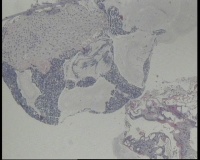

镜下见鳞状上皮大部分如(图1) ,仅局灶鳞状上皮异型(图2-4),细胞似牵拉变形,部分腺腔内见异型细胞团,这些细胞跟LEEP刀手术电凝有关系吗?这个怎么报?累腺明显,上皮图1怎么报?能报CINII—III累及腺体吗?还是宫颈高级别鳞状上皮内病变累及腺体

图3

CIN2-3累腺,有机械损伤,要按1-12点分别报告,要报告内外切缘情况。